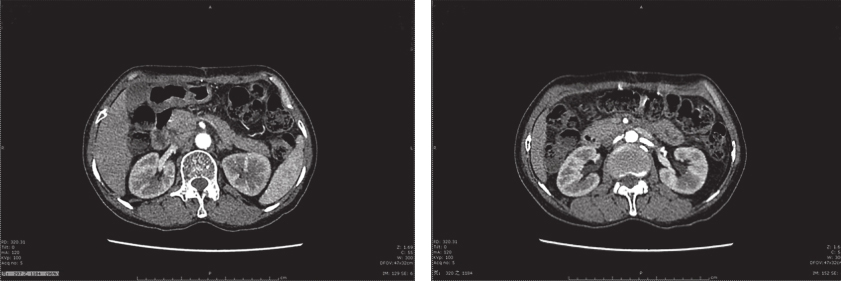

患者术后出现不全梗阻症状,经禁食、肠内营养等对症支持治疗,患者术后30天可完全经口进食,予以出院。出院后予以伊马替尼400mg/d治疗。截至目前,共随访15个月,未见肿瘤复发转移征象(图3)。

图3 术后1年腹部增强CT